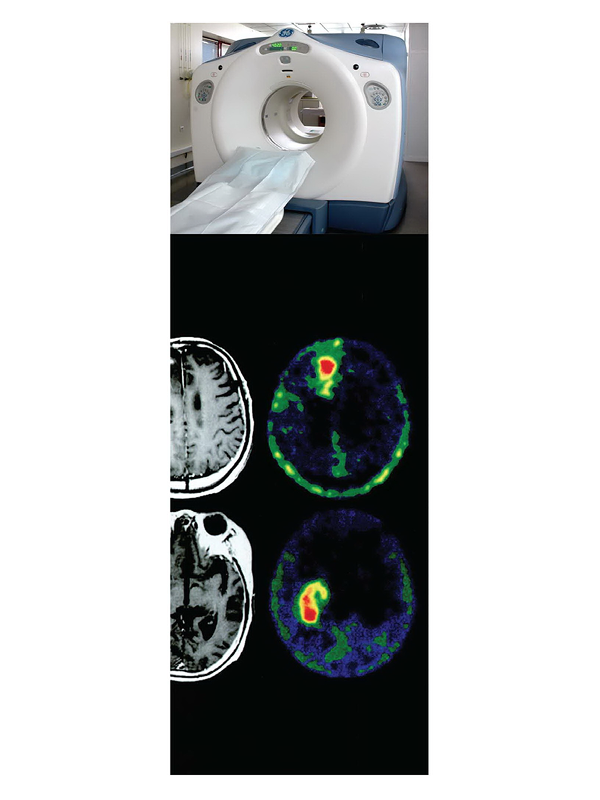

การศึกษาความเป็นไปได้และความเหมาะสมของการใช้เทคโนโลยีเพทซีทีในประเทศไทย